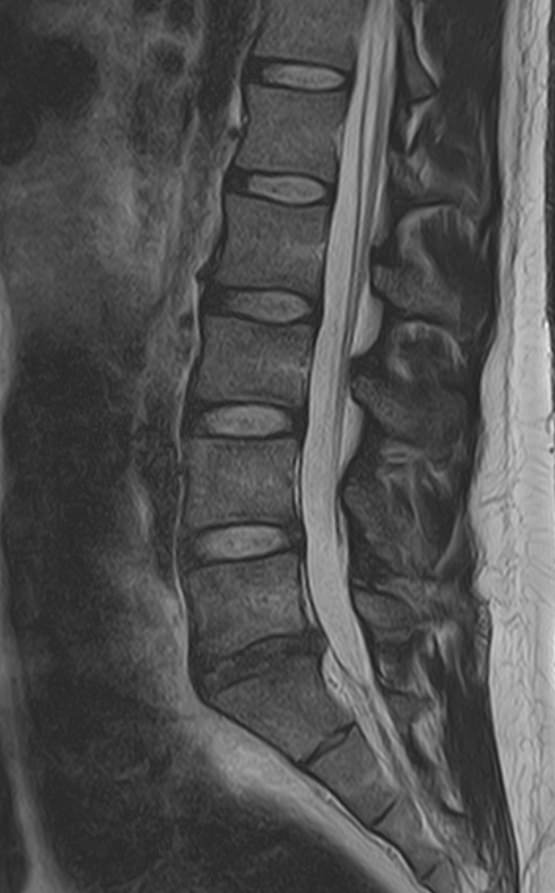

Наиболее точным и эффективным способом диагностики причин появления болей в нижней части спины является МРТ пояснично-крестцового отдела позвоночника. С помощью данного метода можно оценить состояние всех анатомических структур позвоночного столба на исследуемом уровне, безошибочно выявить происхождение болевого синдрома и назначить своевременное лечение.

Многим пациентам интересно, что показывает МРТ пояснично-крестцового отдела. Высокая детальность получаемых с помощью МР-диагностики изображений позволяет с точностью выявить следующие заболевания, локализующиеся в области поясничного отдела позвоночника:

• протрузии и грыжи межпозвонковых дисков;

• дегенеративные заболевания: остеохондроз, спондилез, спондилоартроз;

• последствия перенесенных травм, такие как компрессионные переломы, подвывихи и смещения позвонков;

• новообразования первичного и вторичного генеза;

воспалительные и деструктивные изменения позвонков и окружающих мягких тканей.